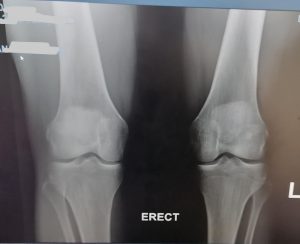

KNEE REPLACEMENT

As the knee ages it may come to a point where cartilage has eroded away to expose bone. Bone grinding on bone as a person is walking is very painful. Fortunately orthopaedic science has evolved to a solution whereby the knee can be replaced with a mechanical prosthesis.

Presently, the results are generally very good with excellent pain relief and mobility after the operation. Longevity of the prosthesis has improved to a point where the 10 year survival is more than 95% in some series.

As all surgery, the procedure is not entirely risk free. Deep venous thrombosis at 1% incidence and infection at 0.4% are most common complications, but stiffness, bleeding, nerve injury etc. can occur.

Below see the pre operative pictures of a normal knee, a diseased knee and a replaced knee.